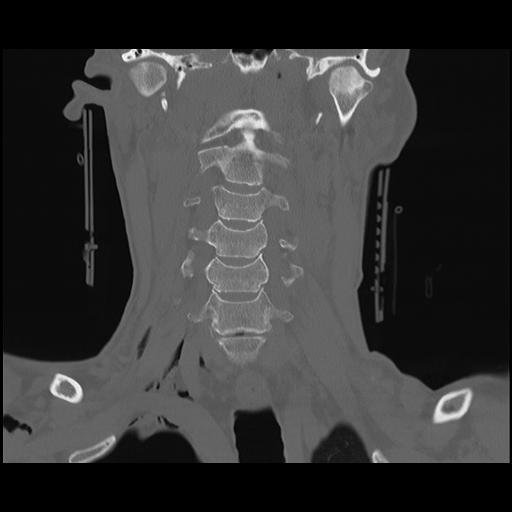

16 HUESO,,Coronal,2.000,HUESO,Coronal,